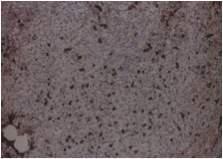

Excisional biopsy of submandibular gland with a diagnostic testing was performed. It showed lymphoid infiltrate with marked atrophy and perilobular and septal sclerotic fibrosis. The lymphoid infiltrate mainly consisted of small lymphocytes and large number of plasma cells. Immunohistochemical studies found most of the plasma cells positive for IgG and IgG4. So, the pathology suggested chronic sclerosing sialadenitis, consistent with IgG4-related disease. The ampulla specimen obtained in previous ERCP was also positive in IgG4 staining. The serum IgG4 level was checked and elevated to 102.9 g/L (normal range <2).

We reviewed the case and requested IgG4 staining for the transbronchial biopsy that obtained 3 months ago. The resulted showed many of the plasma cells positive cytoplasmic staining for both IgG and IgG4 (Fig 4A, 4B, 4C, 4D). It confirmed the pulmonary involvement of IgG4-related disease.